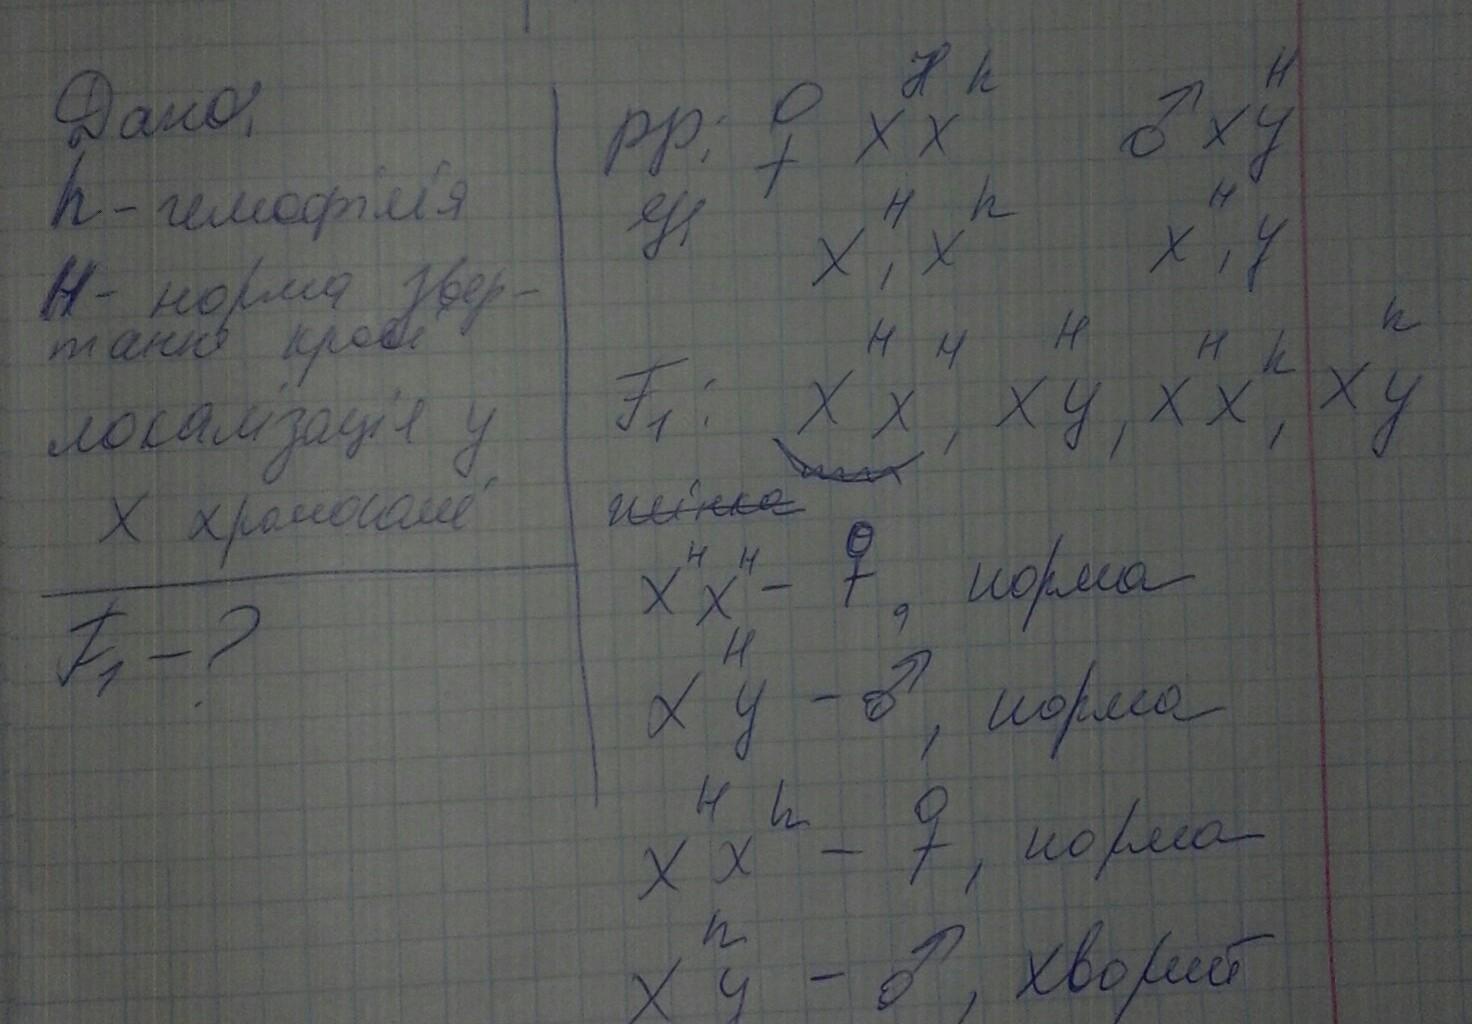

Генетика гемофилии: рецессивные гены и их проявления